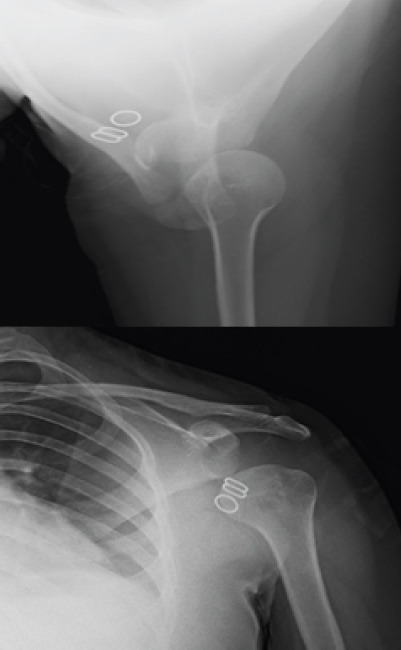

Case report: We report a unique case of a 15-year-old female who presented with chronic, atraumatic left shoulder subluxation, persisting over 18 months. The patient experienced pain and limited range of motion but reported no history of injury. Multiple prior consultations yielded temporary relief with analgesics, and no definitive diagnosis was established. Clinical evaluation revealed limited active abduction and external rotation with no signs of ligamentous laxity or neurological involvement. Radiographic assessment demonstrated gross inferior subluxation of the humeral head. Magnetic resonance imaging and computed tomography imaging confirmed intact soft tissue structures with mild joint effusion, anterior glenoid flattening, and a 6% glenoid bone loss. A diagnosis of inferior, non-positional, controllable idiopathic FSI was made, likely due to deltoid atony.